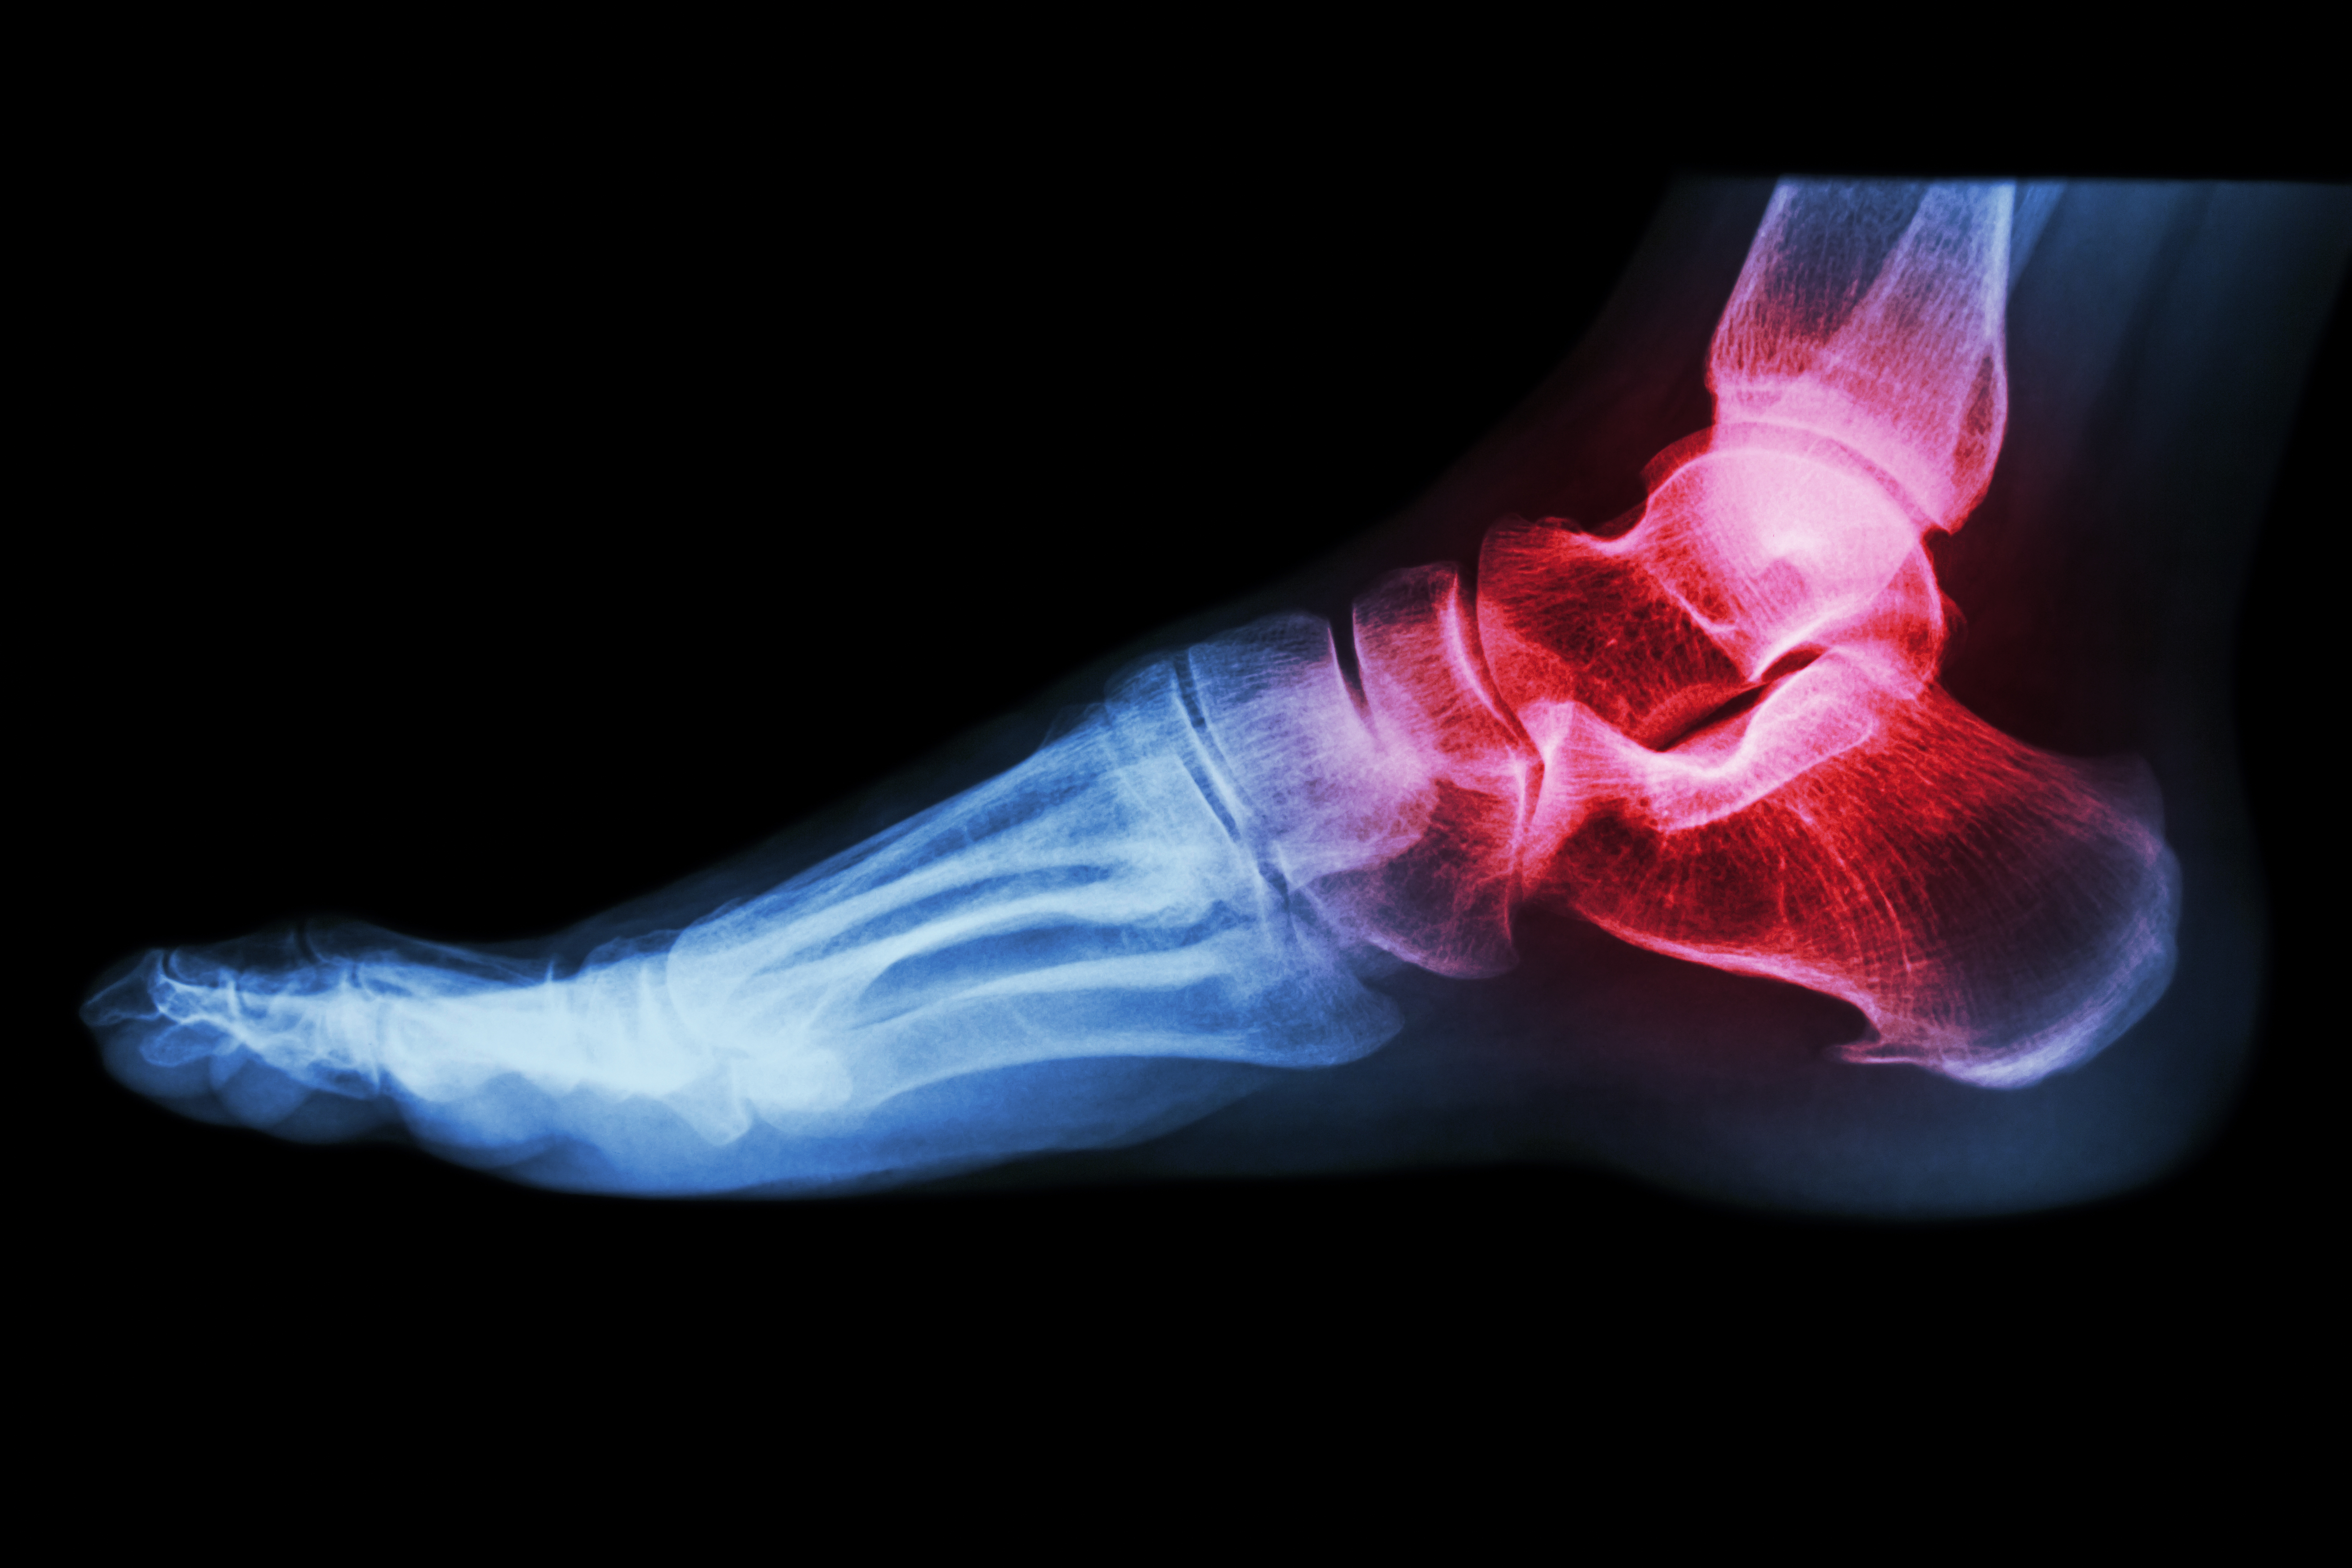

• Fish oil: If you have inflammatory arthritis (red, swollen joints, as in rheumatoid arthritis) add fish oil (1 teaspoon or 3 capsules 2-3 times a day for 6 weeks, then once a day).